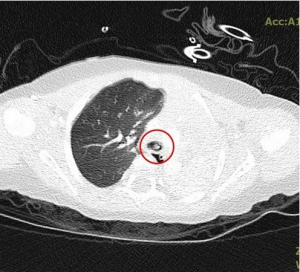

六月十八日凌晨,一名11個月大的女嬰因出現呼吸不暢等缺氧症狀,被緊急送往花蓮慈濟醫院,經急診團隊初步檢查,發現是吸入異物造成氣管阻塞,後續小兒部團隊利用支氣管鏡,將堵塞左邊支氣管的異物夾出,二天後女嬰從兒童加護病房轉至普通病房,並在二十一日平安出院。花蓮慈院兒童急重症科主任裘品筠表示,一般一至二歲以下的嬰幼兒處在口腔期,可能會經常拿到東西就往嘴裡塞,呼籲家長將家中的小物品妥善收起,以避免不慎被孩子誤吞,嗆入氣管或滑進食道。

左圖:X光影像顯示孩子的左邊肺部已經呈現白色塌陷狀態。

右圖:將異物取出後氧氣進入,孩子的左肺部不再塌陷,恢復正常充氣狀態。